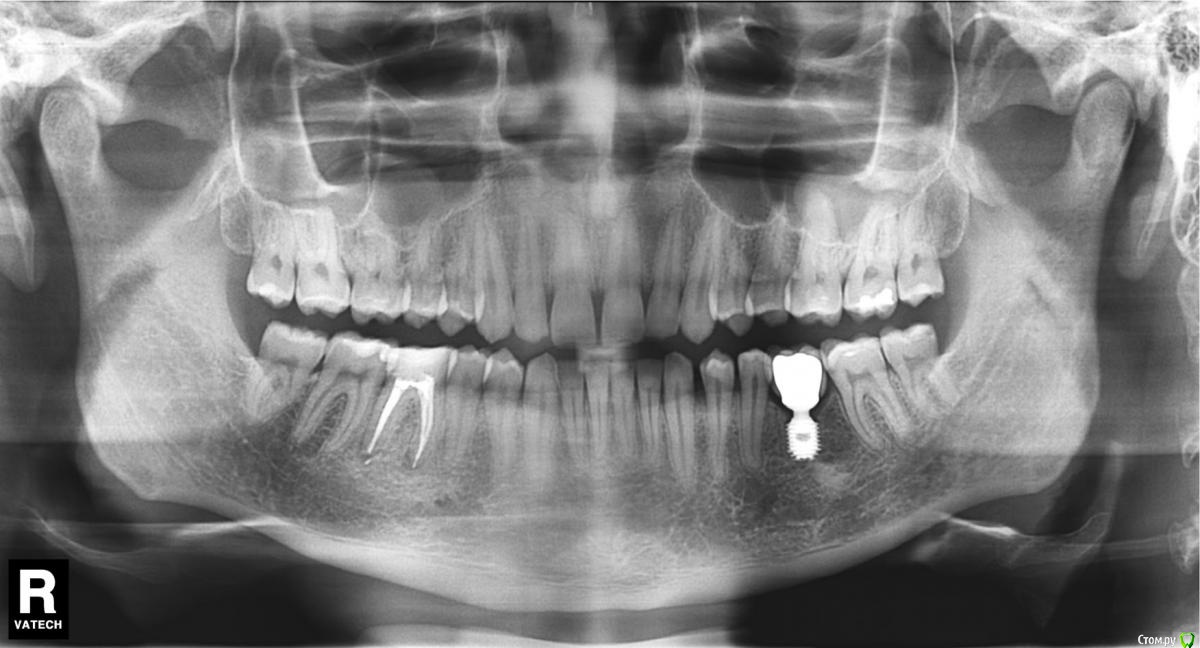

bobrdobr Опубликовано 27 августа, 2016 Автор Поделиться Опубликовано 27 августа, 2016 И вновь здравствуйте! С момента имплантации прошло почти 1,5 года. Все же, поставил байкон. Считаю, что успешно. Отзыв оставил в соответствующей теме. А вот что имею на сегодняшний день: Ссылка на комментарий

Доктор Хаус Опубликовано 28 августа, 2016 Поделиться Опубликовано 28 августа, 2016 (изменено) По ОПТГ все стабильно, покажите внутри ротовое фото. Изменено 28 августа, 2016 пользователем Доктор Хаус 1 Ссылка на комментарий

bobrdobr Опубликовано 26 марта, 2021 Автор Поделиться Опубликовано 26 марта, 2021 (изменено) 6 лет с момента имплантации. Жалоб нет. Видно, что кость немного наросла по сравнению с предыдущим снимком. Наконец купил ирригатор, недооцененная вещь. Bicon данный хирург ставить, как я понял, перестал - имплант дает небольшую усадку. Изменено 26 марта, 2021 пользователем bobrdobr 2 Ссылка на комментарий

red_butler Опубликовано 28 марта, 2021 Поделиться Опубликовано 28 марта, 2021 на снимке все отлично 1 Ссылка на комментарий